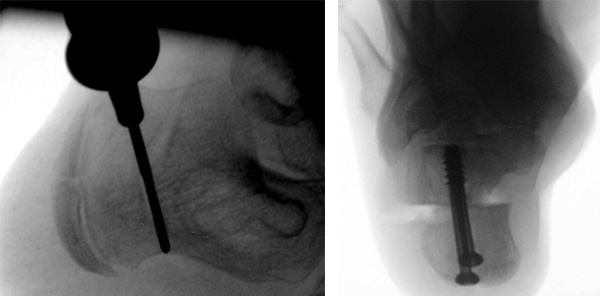

Der Bildverstärker steht links des OP Tisches. Der Zentralstrahl wird für die seitliche Aufnahme im 90° Winkel zur Kalkaneusachse ausgerichtet. Das nicht zu operierende Bein ist etwas abgesenkt.  Für die axiale Aufnahme ist der Bildverstärker maximal nach kaudal gekippt, der Zentralstrahl ist auf die Ferse zentriert und verläuft weitgehend parallel zur Osteotomieebene (Abb. 7a und b).

Der Operateur steht vor dem rechten Fuß. Die Maschine für das Fräsensystem steht auf der linken Seite des Operateurs. Der Monitor steht für den Operateur gut sichtbar auf der linken Seite neben dem Bildverstärker (Abb. 8a und b).

Die seitliche Aufnahme erlaubt die Beurteilung der Lage der Fräse, auf der axialen Aufnahme kann das Ausmaß der Verschiebung exakt beurteilt werden. Die Lage des Osteosynthesematerials wird grundsätzlich in beiden Ebenen kontrolliert (Abb. 8c und d).